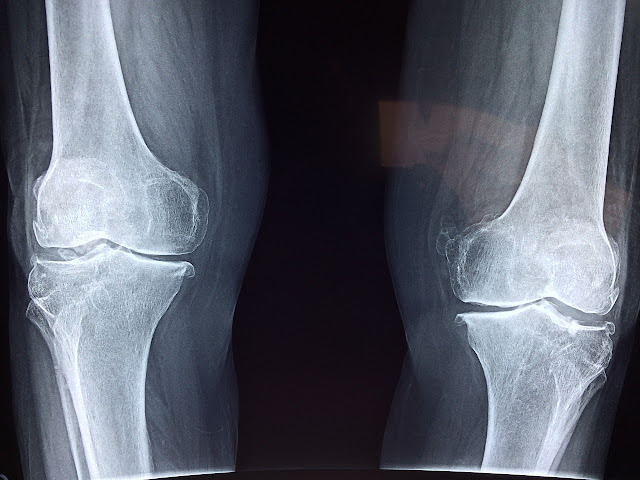

Knee pain is a common ailment that affects people of all ages. It can be caused by a variety of factors, including injury, overuse, and underlying medical conditions. Understanding the causes of knee pain is crucial in order to address it effectively and prevent further damage.